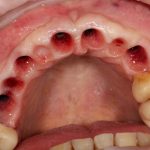

Вот клиническая картина через 4 месяца после ранее проведенной имплантации с остеопластикой:

Как видишь, коллеги из недалекой дружественной страны не осилили снятие швов. Мне это не нравится, хотя и объясняет, почему люди готовы ехать за тыщи километров ради 20-минутной операции удаления зуба мудрости.

Ну хорошо. Швы сняли. Делаем разрез. Обрати внимание, что после всех проведенных операций у нас остается очень небольшой по ширине слой жевательной слизистой оболочки: